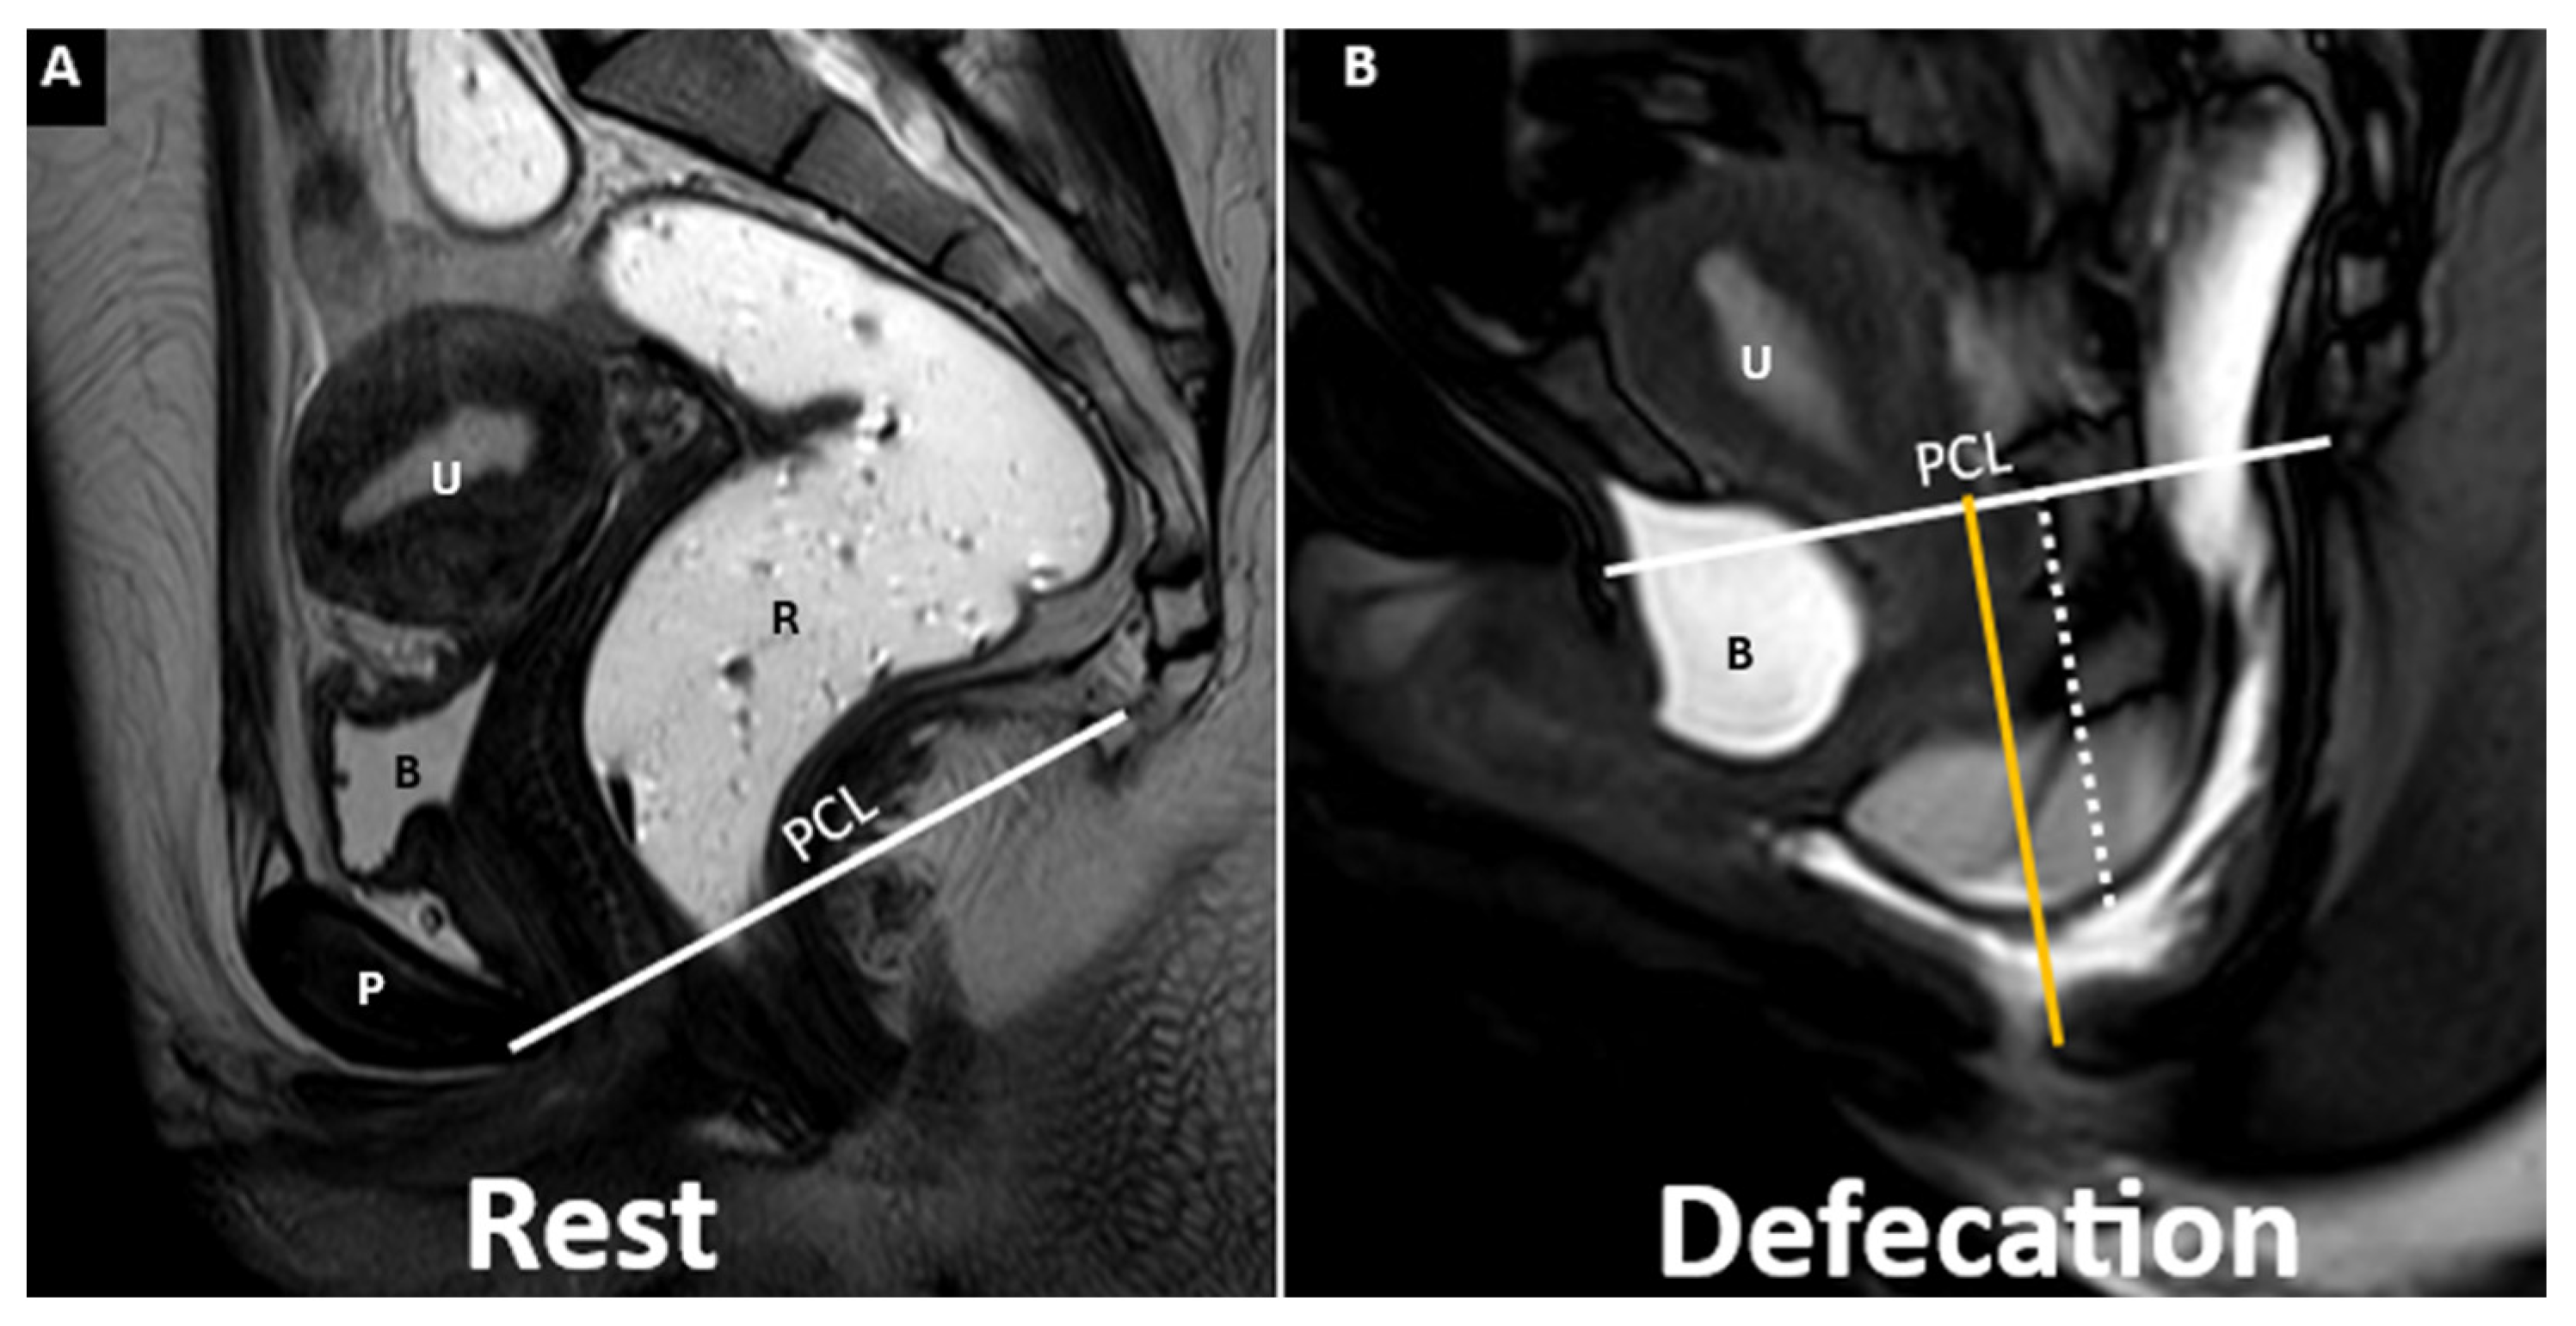

| Pubococcygeal Line (PCL) | Line from the inferior pubic border to the last coccygeal joint | Baseline for measuring organ descent | PCL Compartment Staging Stage 0: Above PCL Stage I: Descent <3 cm below PCL Stage II: Descent 3–6 cm below PCL Stage III: Descent >6 cm below PCL Stage IV: Complete organ prolapse |

| H Line (Hiatal Line) | Distance between the inferior pubic border and the anorectal junction | Assesses puborectal hiatus (anteroposterior dimension during straining) | POP Grade Hiatal Enlargement Normal: <6 cm Mild: 6–8 cm Moderate: 8–10 cm Severe: >10 cm |

| M Line (Muscle Line) | Perpendicular line from the PCL, measuring organ descent | Evaluates posterior pelvic organ descent | Pelvic Floor Descent Normal: <2 cm Mild: 2–4 cm Moderate: 4–6 cm Severe: >6 cm |